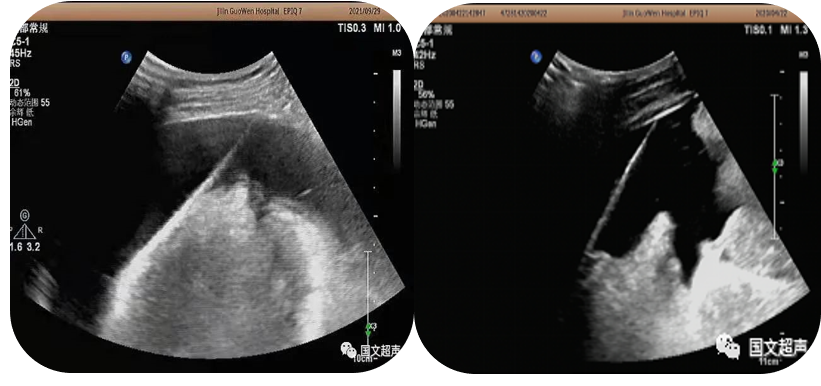

2.超聲引導下置管引流

超聲實時引導下將引流管放置在胸腹腔積液,臟器及間隙膿腫內(nèi)抽取積液減輕癥狀,亦可將藥物注入到某些特定部位從而達到治療效果。

經(jīng)皮肝膿腫穿刺引流

心包積液穿刺引流/腹腔積液穿刺引流